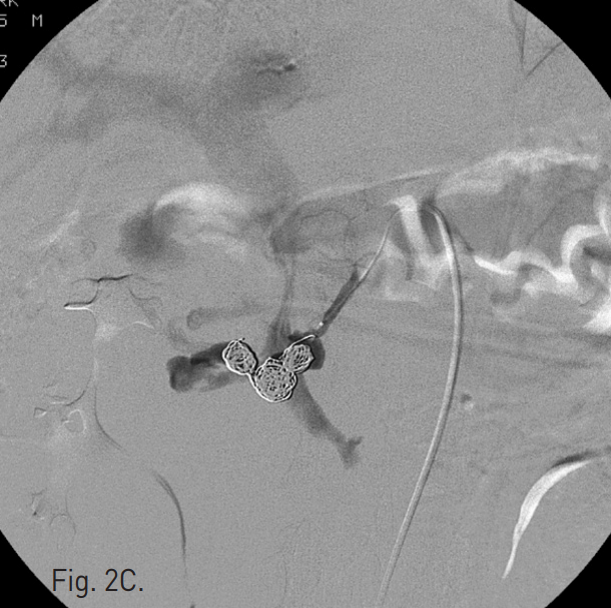

C. Multiple coil deployment was performed but the arteriovenous fistula is still remained.

초음파 및 투시 하에서 우측 대퇴동맥을 천자하고 5F Cobra catheter(Cook, Bloomington, IN, USA)를 이용하여 복강동맥 및 상장간막동맥 조영술을 시행하였다. 복강동맥 조영술에서 dorsal pancreatic artery에서 유출되는 조영제의 누출과 거짓동맥류를 확인하였고 상장간막 정맥으로의 동정맥루를 확인하였다(Fig. 2A, B). Microcatheter(Renegade, Boston Scientific, Natick, MA, USA)를 이용하여 이 거짓동맥류를 선택하였고, 10mm Interlock coil(Boston Scientific, Natick, MA, USA) 6개와, 10mm Nester coil(Cook, Bloomington, IN, USA) 3개를 사용하여 embolization을 시행하였다(Fig. 2C). 이후 남아있는 거짓동맥류와 동정맥루에 대하여 NBCA와 lipiodol mixture(3:1)를 이용하여 색전술을 시행하였다. 시술 후 동맥조영술에서 남아있는 거짓동맥류나 상장간막 정맥으로의 동정맥루는 보이지 않았다(Fig. 2D).